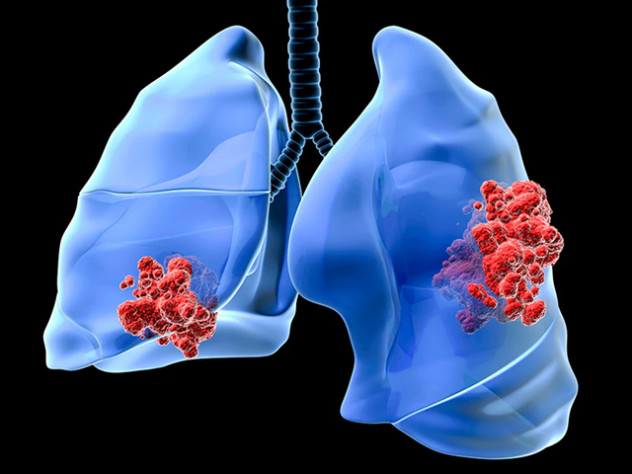

Ученые выяснили, какие математические модели точнее прогнозируют реакцию опухоли на терапию рака легкого

Ученые Центра математического моделирования в разработке лекарств Сеченовского Университета провели первое в своем роде сравнительное исследование пяти наиболее широко используемых моделей на основе клинических данных 381 пациента с немелкоклеточным раком легкого. Результаты работы опубликовали в научном журнале «CPT: Pharmacometrics and Systems Pharmacology».